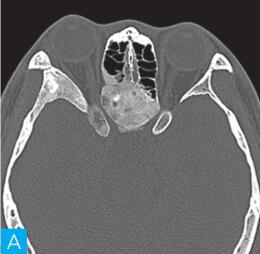

CT检查:检查设备为16层CT,病人采取仰卧位,扫描范围包括双侧鼻窦。扫描参数:层厚2.5mm,120kV,150mA,矩阵512×512。观察图像:软组织窗窗宽300HU,窗位60HU;骨窗窗宽2000HU,窗位400HU,见图1。

图1 鼻窦CT:A. CT横断面(骨窗);B. CT横断面(软组织窗);C. CT冠状面(骨窗);D. CT冠状面(软组织窗)

答案A 解析:结合CT横轴位及冠状位图像,该病变位于后组筛窦,不难判断。

答案D 解析:该病例病变周围骨质在原有后组筛窦结构基础上出现轻度的骨质膨胀性改变,周围骨质可见明显硬化,故D为最佳答案。

CT平扫示后组筛窦区见轻度膨胀性骨质破坏,内部密度混杂,可见斑片状、分隔状骨质密度影,部分呈磨玻璃改变,病变边缘清晰,可见薄层骨壳及硬化边。

发现病变较为容易,主要分析其病变的良恶性。本病例基本征象为病变区域呈轻度膨胀性骨质破坏,邻近骨质呈轻度压迫性骨质吸收,边缘可见硬化边,提示病变慢性进展过程,病变内部密度欠均匀,以软组织密度以及磨玻璃样高密度为主。

对于本病例来说,病变定位不困难,病变主体位于后组筛窦区。

本病例CT上特点为轻度膨胀性压迫性骨质吸收,边缘骨质见硬化边,呈薄层骨壳表现,提示肿瘤良性可能;病变内部密度不均匀,可见骨性间隔及斑片状磨玻璃骨性密度影,提示病变可能为骨纤维源性肿瘤或肿瘤样病变。

本病例的临床表现无特异性。影像学表现具有一定特征性,具有诊断价值。病变主体位于后组筛窦,精准的病变定位是该病例的诊断前提。病变区骨质呈轻度膨胀性骨质破坏,边缘可见明显硬化边,提示病变进展缓慢,是良性病变的特征。另外,CT显示病变内部有大量磨玻璃样高密度影,提示病变区存在纤维化骨的成分,是骨纤维源性肿瘤或肿瘤样病变的重要影像学征象。结合病变发生的部位,好发于颅面骨的骨纤维源性良性肿瘤常见有骨化性纤维瘤、骨纤维异常增殖症。本例不支持骨纤维异常增殖症的地方在于,后者发生在颅面骨时一般呈多骨受累改变,同时病变本身骨质膨胀变形更明显。

本病例定位不难,病变主体位于双侧后组筛窦区域。病变区呈轻度膨胀性骨质破坏,内部以软组织密度成分为主,正常筛窦的骨性间隔破坏消失,边缘骨质硬化,提示病变进展速度相对缓慢,对于病变的良恶性定性有一定价值,考虑病变为良性病变。

除此之外,我们需注意病变内部变异出现了大片状磨玻璃样骨性高密度影;一般来说,骨内病变出现磨玻璃密度,极大可能提示病变可能为骨纤维源性肿瘤,其病理上多数是由于纤维化骨不完全所致。需要了解的是,发生于颌面骨的骨纤维源性良性肿瘤或肿瘤样病变较为常见的是骨化性纤维瘤和骨纤维异常增殖症,两者在病理水平较难鉴别,但在影像学表现上有各自的特点。骨化性纤维瘤主要发生于颌面骨,一般以单骨受累为主,因组织分化不同,内部成分多混杂,可出现软组织密度、囊性密度、磨玻璃密度以及骨性密度等;另外骨化性纤维瘤外周一般会有较为明显的骨壳包绕,也是诊断要点。而发生于颌面骨的骨纤维异常增殖症,一般呈多骨受累,同时骨质膨胀变形较骨化性纤维瘤更为明显。

与骨化性纤维瘤比较,骨纤维异常增殖症骨质密度相对均匀,主要以磨玻璃样密度为主,外周出现骨壳的概率也较小。结合本病例,病变主要以单骨受累为主,呈轻度膨胀改变,其内部密度不均伴有磨玻璃密度改变,边缘呈薄层骨壳样改变,应该考虑到骨化性纤维瘤的诊断。